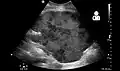

Imaging

Postoperatively, kidneys are periodically assessed by ultrasound to assess for the imaging and physiologic changes that accompany transplant rejection. Imaging also allows evaluation of supportive structures such as the anastomosed transplant artery, vein, and ureter, to ensure they are stable in appearance.

-

Postoperative bleeding following kidney transplant as seen on ultrasound[86]